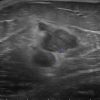

Di căn vú

Di căn vú - Ảnh 3

» Thông tin: Nữ giới – 70 tuổi.

» Lâm sàng: Khối tuyến vú / K hắc tố.